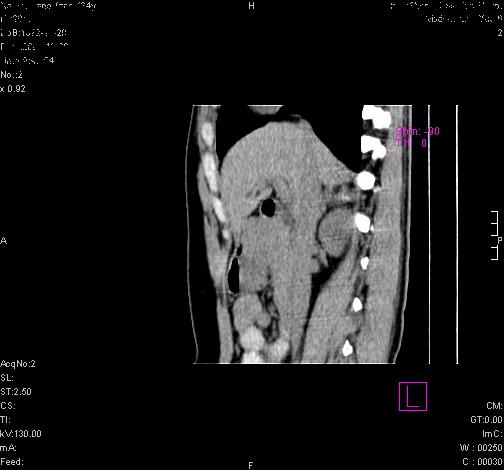

标题: CL0340:【】肾上腺囊肿,比较典型。

患者为年轻女性,查体发现右侧肾上腺囊性占位。无临床体征。

这么漂亮的图像,一看一目了然。典型的右侧肾上腺囊肿,周围有钙化。感谢搂主!

这么明显的弧形钙化,多考虑包虫病所致的寄生虫性囊肿。

右侧肾上腺囊性密度灶囊壁有钙化。考虑肾上腺囊肿,结核?

右侧肾上腺囊肿,周围有钙化。